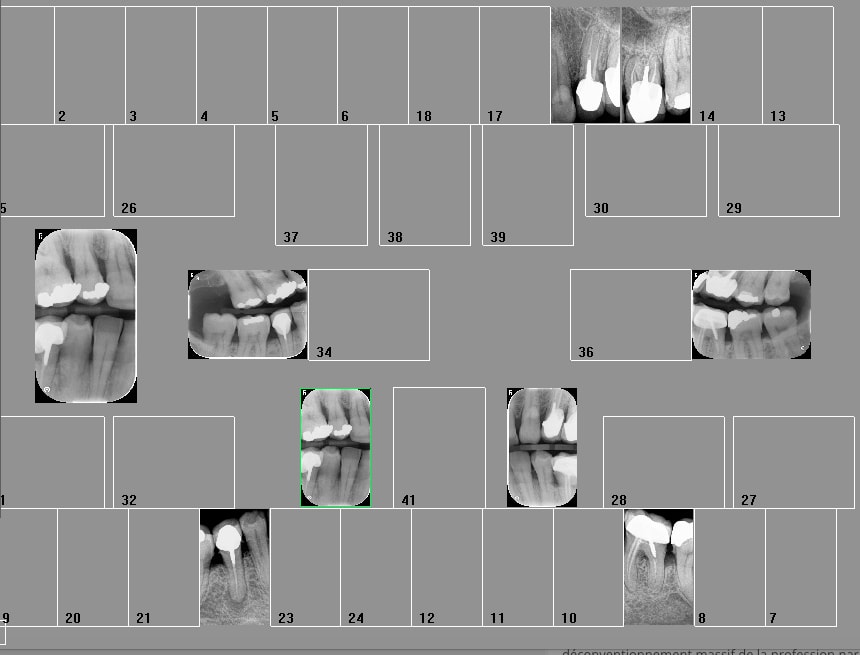

Pourquoi opposer les 2 systèmes ? Hein ? Je n'utilise les plaques que pour les rétro coronaires ( faut un capteur taille 2), je n'ai que 2 taille 1) . Pour le reste capteur. Et pour la définition capteur supérieur un seul temps d'exposition 0,09 s pour les plaques c'est à géométrie variable Jusqu'à 0,39 s par cliché. De plus une protection par cliché ca c'est vraiment la merde.

Comme ca ? 4 développements ca suffit pour les rétro coronaires. je me vois mal en faire 24 pour les 2 arcades complètes. -)